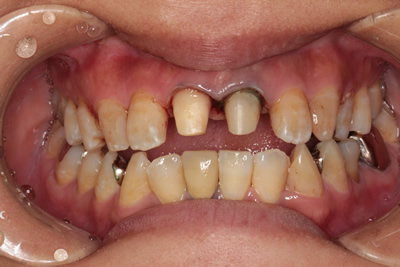

金属の土台による、歯の黒変が歯肉を透けてグレーに見えています。

ファイバーコアに交換。歯の部分が黒く変色しているのがおわかりになりますでしょうか。この後はBOPTテクニックを用いた被せ物で歯肉の厚みを増やし、黒変が透けないようにして補綴処置を行いました。